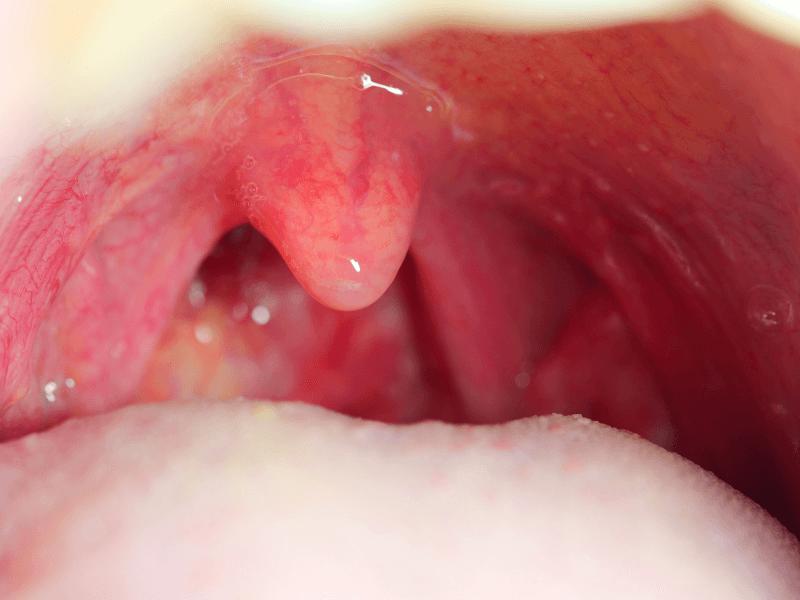

Nếu thấy có các biểu hiện mắc bệnh, bác sĩ sẽ chỉ định nội soi tai mũi họng với mục đích phát hiện những tổn thương bất thường. Nội soi tai mũi họng giúp các bác sĩ có thể quan sát rõ khu vực bên trong vòm họng nhờ hình ảnh mà camera thu nhận được, cho hình ảnh phóng đại gấp 30 lần. Camera thường được gắn vào đầu dây ống mềm, luồn qua mũi, tai và họng của người bệnh.